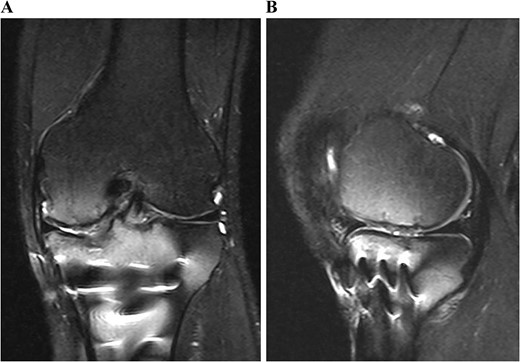

A 49-year-old male patient fell while playing soccer and visited our hospital with severe pain and swelling in his left knee. A lateral-view plain radiograph showed articular depression of the tibial plateau (Fig. 1). Three-dimensional reconstructed computed tomography (CT) scan revealed a 5-mm depression of the medial articular surface and a split in the medial plateau (Fig. 2). The fracture was classified as AO/OTA 41B3.2 and Schatzker type 2 [6, 7]. MRI scan showed a medial femoral cartilage injury that appeared as a kissing lesion opposite the tibial fracture. The length and width of the cartilage defect on the femoral condyle were 18 mm and 20 mm, respectively (Fig. 3). A part of the peripheral cartilage around the defect was suspected to be delaminated, and the defect was estimated to exceed 4 cm2.

Preoperative T2-weighted magnetic resonance images of the left knee. A cartilage injury of the medial femoral condyle appeared as a kissing lesion opposite the tibial plateau fracture. The coronal image revealed a 20-mm-wide cartilage injury (A). The sagittal image showed an 18-mm-long cartilage injury (B).